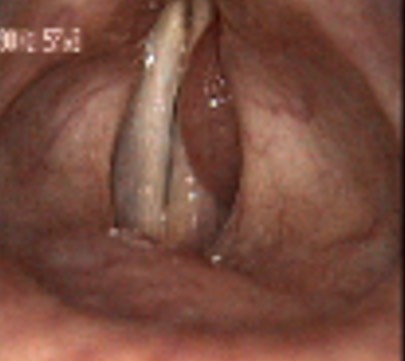

2642. Данная ларингеальная картина характеризует